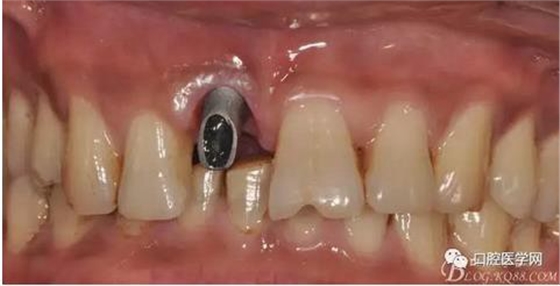

圖7 術后植入愈合基

圖8 術后即刻臨時冠修復

圖9 三個月后袖口形成正位照